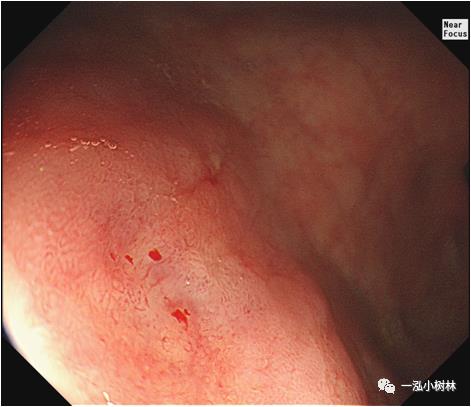

图4a 白光内镜:胃体下部高分化腺癌(Tub1)

图4b 白光内镜:胃体下部高分化腺癌(Tub1)

图4c NBI+ME:表面构造呈绒毛样,大小不等、形态不规则,边界清晰,诊断为0-IIc早期胃癌,分化程度:高分化腺癌(Tub1),深度:黏膜内。活检病理:高分化腺癌/高级别内瘤变。